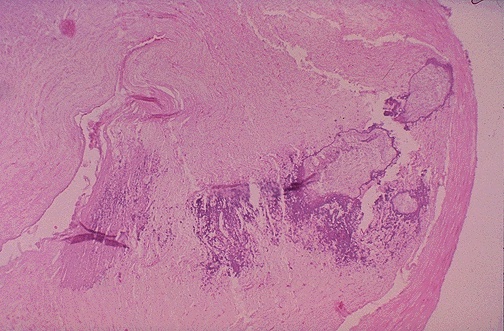

This cross section of coronary artery demonstrates occlusive atherosclerosis complicated by calcification (the blue material in this section).